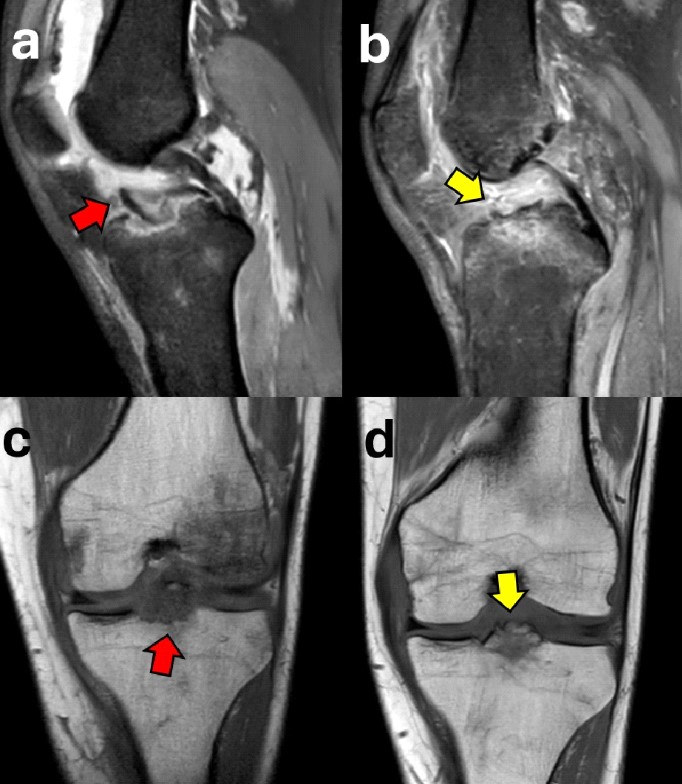

Conventional X-rays are often used as the initial diagnostic tool to identify fractures. CT scan is generally used in ambiguous cases and to better determine the degree of displacement4 (Figure 1). Based on that, the fracture can be classified according to the Meyers and McKeever’s classification in: Type I: minimally/nondisplaced fragment (< 3 mm); Type II: anterior elevation of the fragment; Type III: complete separation of the fragment (Type IIIa involves a small portion of the eminence; Type IIIb involves the majority of the eminence); Type 4: comminuted avulsion or rotation of the fracture fragment5. Alternatively, Green et al6 highlight the key role of MRI in the assessment of tibial eminence fracture because of the possibility to identify associated injuries such as meniscal tears (Figure 2) or ligamentous damage6,7. In our experience, additional soft tissue injuries such as meniscal entrapment or ACL injuries are identified alongside the fracture in a substantial number of cases8-10. The treatment approach depends on the severity of the fracture, with nondisplaced fractures often treated conservatively with immobilization in extension for 4-6 weeks11. However, in cases where there is a significant displacement, surgical intervention is typically required to prevent long-term instability, nonunion, or malunion12. Different surgical approaches have been proposed to manage tibial avulsion fractures. Among them, Arthroscopic Reduction and Internal Fixation (ARIF) has gained increasing preference over open techniques due to its minimally invasive nature, fast recovery times, and limited complications.

Case 3: A 24-year-old female tennis player sustained a left knee sprain while skiing. The initial X-ray was interpreted as negative, and the patient was initially treated conservatively in another institution. Due to the lack of extension, the patient underwent an MRI, which showed a Meyers and McKeevers Type III fracture (Figure 14a, c) with medial meniscus entrapment, medial meniscus posterior horn tear, and proximal medial collateral ligament (MCL) injury. After ARIF with absorbable sutures and medial meniscus repair performed 22 days after injury, good reduction and healing were obtained at the 8-week follow-up evaluation (Figure 14b, d). However, due to the late treatment, the patient developed arthrofibrosis, which was resolved after 6 months of intense rehabilitation. The patient returned to sport 7 months after injury.

Figure 14. A 24-year-old female with a Meyers and McKeevers Type III fracture (red arrow) in a sagittal MRI scan (a) and the healed and reduced fragment (yellow arrow) 8 weeks after surgery (b); coronal pre-operative (c) and post-operative (d) views of the same patient.